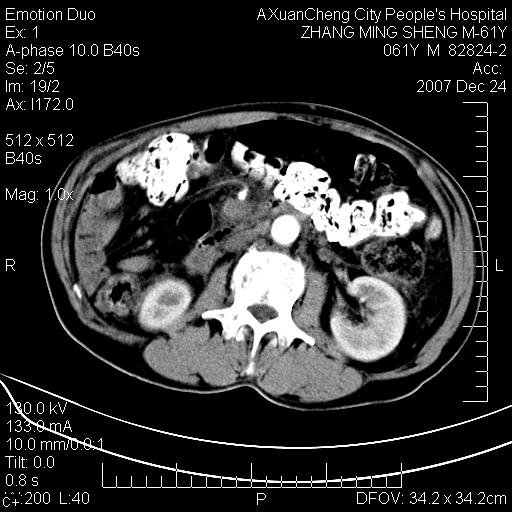

标题: CT11031:M61Y,胰腺占位

大家侃侃门静脉和胆管系统怎么回事,肝内转移?

胰腺癌肝转移

2,肝内多发结节状低密度占位,伴门脉及肠系膜上v栓子形成.考虑a;门脉及肠系膜上v血栓后肝改变.b;弥漫型肝癌伴门脉及肠系膜癌栓.

肝硬化,门脉高压,脾肿大;弥漫性肝癌,肝内、门脉、腹膜后淋巴结转移,肝内外胆管扩张,胰头区占位,建议mr检查

胰腺癌伴肝内转移;门脉、肠系膜上v癌栓形成。

考虑为:胰腺癌伴肝脏转移、腹膜后淋巴结转移,门静脉及肠系膜上静脉瘤栓形成。

胰体尾癌伴肝内转移,门静脉及肠系膜上静脉瘤栓形成.